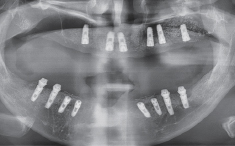

수술 전 파노라마

수술 후 파노라마